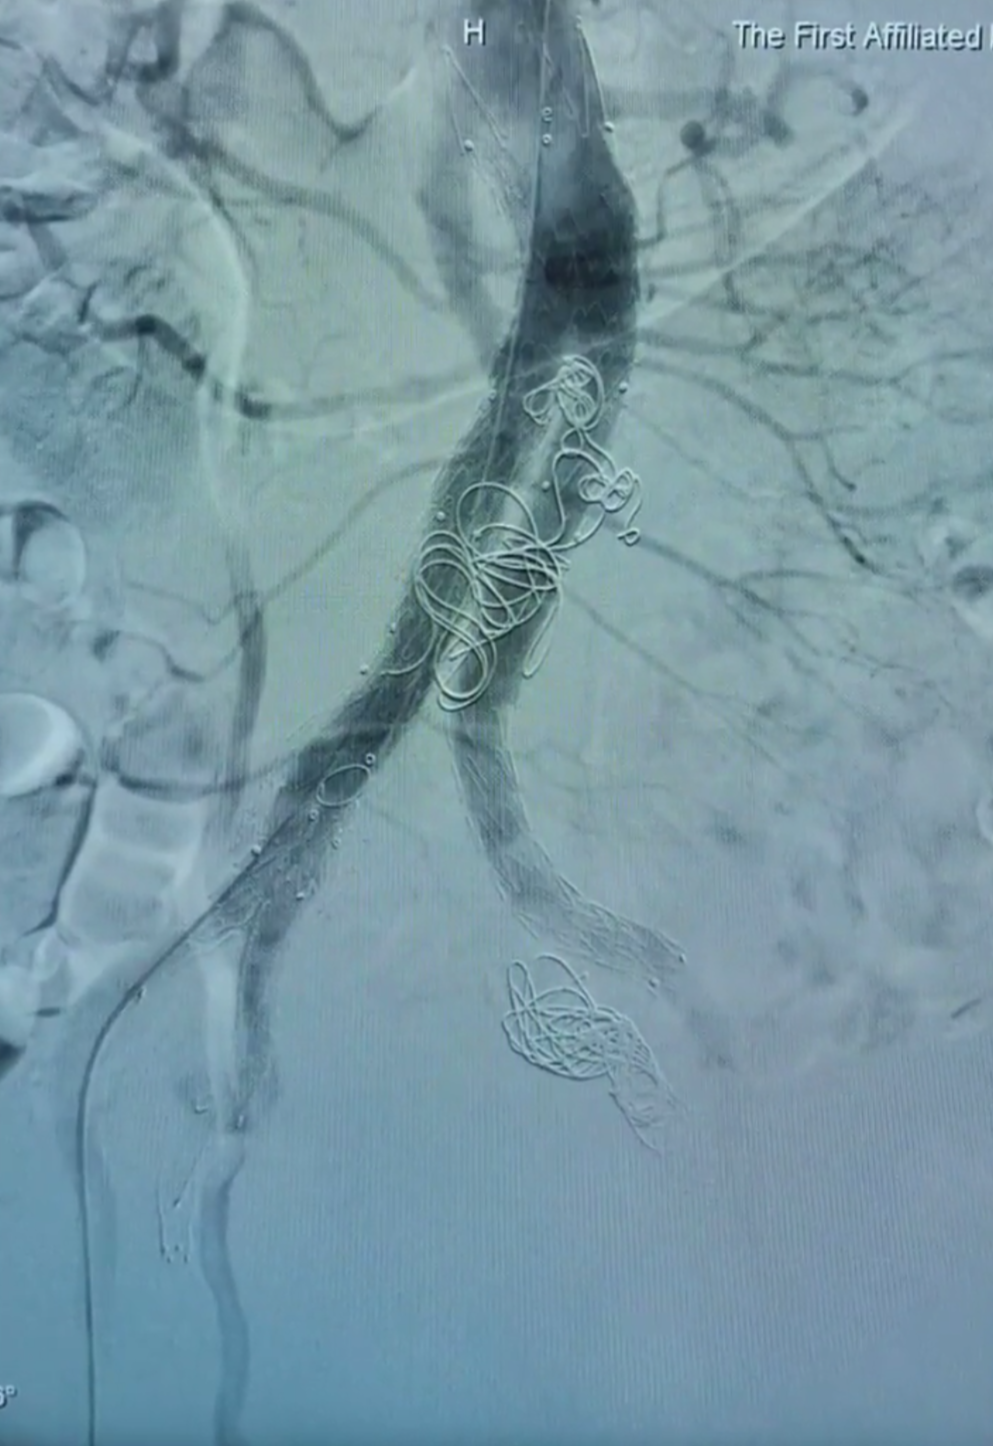

瘤囊血栓化,髂支动脉通畅,患者预后良好

整体造影动脉瘤隔绝,髂内外通畅,术后1月随访,预后良好

68岁男性 ,因腹主动脉瘤及双侧髂总动脉瘤入院。左侧采用商品化IBE支架、右侧行栓塞。术中利用牵引导丝快速超选髂内完成重建 ,右侧引入腹主主体 ,通过喇叭腿与IBE衔接 ,造影隔绝瘤腔 ,术后1月随访显示瘤体隔绝良好 ,左侧髂外分支通畅。

利用牵张导丝,快速超选髂内,完成髂内重建

右侧引入腹主主体,喇叭腿与IBE桥接。造影隔绝

术后1月随访,整体隔绝,左侧髂内外分支通畅